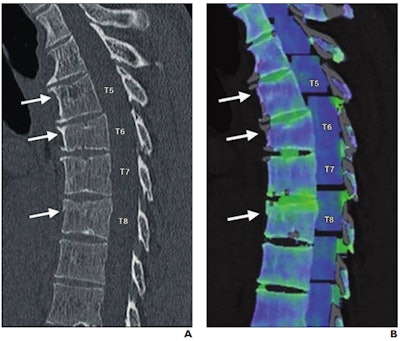

59-year-old man involved in skiing accident. (A) Sagittal reformatted bone window CT image of thoracic spine shows wedge-shaped deformity at T6 and subtle superior endplate deformities at T5 and T8. Arrows denote deformities. (B) Color-coded dual-energy CT shows only T8 deformity is associated with bone marrow edema; T5 and T6 deformities likely represent chronic fractures. Arrows denote deformities. Images and caption courtesy of the American Roentgen Ray Society.Of the 3,159 exams, dual-energy CT was not mentioned in the report in most cases (71.9%). But in those cases that did make use of the technique, dual-energy CT potentially altered clinical management in 9.4%, increased diagnostic confidence in 14.4%, offered relevant new information in 5.6%, and helped characterize incidental findings in 1.4% of cases. Dual-energy CT altered patient management most in the musculoskeletal category, at 89%; of these, 70% of the exams were performed to confirm gout.